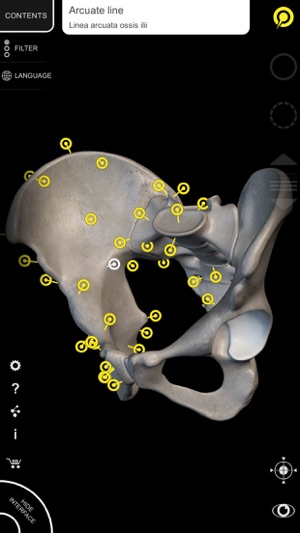

By selecting models or pins you will be shown the terms related to any specific anatomical part, you can select from 11 languages and show the terms in two languages simultaneously.

• Interactive Pin allow visualization of the term relative to every anatomical detail

• The anatomical terms and the interface are available in 11 languages: Latin,

English, French, German, Italian, Portuguese, Russian, Spanish, Chinese, Japanese and Korean

• The language can be selected directly from the interface of the app

• The anatomical terms can be shown in two languages simultaneously